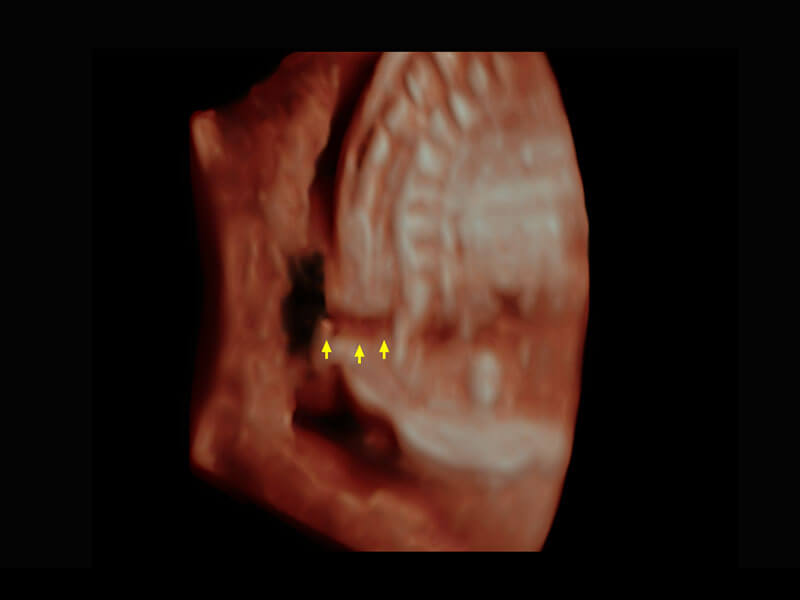

P60搭载一系列胎儿心脏成像技术,实现精细的胎儿心脏评估。

• 胎心容积成像